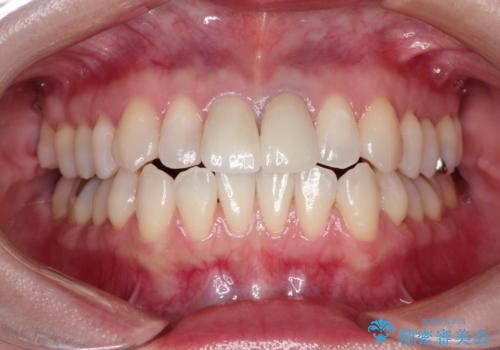

前歯の根元が黒い オールセラミッククラウンの装着による改善

かぶせ物と歯の境目の再設定を行い、適合の良いかぶせ物を装着することで、審美的に自然な状態に改善することができました。